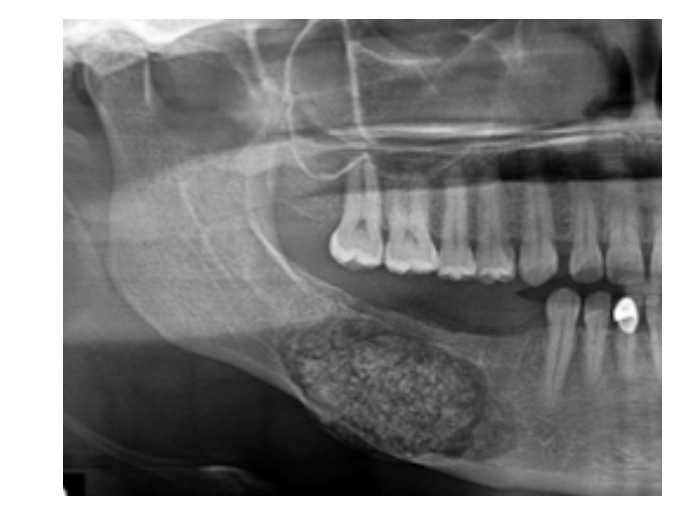

Diffuse Sclerosing Osteomyelitis

Same as Focal, BUT wider scale

* may lead to Jaw fracture

Bone Sclerosis:

* resulting from low-grade inflammation (like chronic pulpitis)